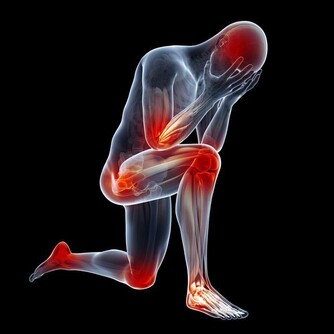

想必大家都聽過“樹老根先枯,人老腿先衰”,現在不僅僅是老年人經常出現膝蓋酸痛,很多的年輕人也會時不時出現膝蓋疼痛,這是因為什麼呢?

不論是跑跳蹲跪,很多生活習慣都會不經意間對膝關節造成影響。

膝蓋不是身體中最常受傷的部位,卻是最薄弱、要求最高的關節,原因是它們經常承受的人的整個重量,而且由於活動範圍大,其結構使它們比髖關節和踝關節更在衝擊下更脆弱。